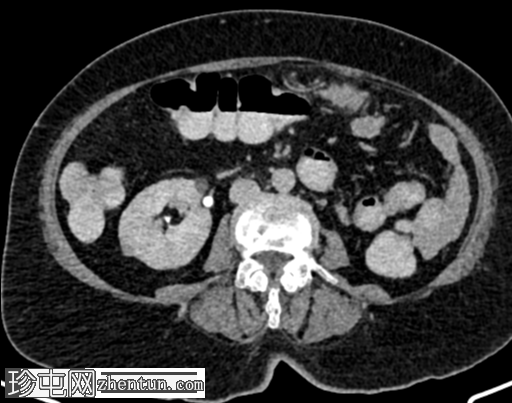

4.png

轴位增强扫描

延迟期

左侧盆壁可见一管状扩张(直径16.5 mm)的充满液体的结构,该结构在S1椎体水平突然向上变窄,然后继续向上延伸,形成轻度强化的纤维条索状结构,直至L5椎体上终板水平。扩张管状结构的尾端逐渐变细,可能终止于阴道穹窿左侧角。在管状结构的尾端可见数个微小的高密度灶,可能为下垂性病灶(其中一个大小为 3.3 mm,315 HU)——可能为结石或钙化。未见其他左侧输尿管样结构。未见左侧膀胱输尿管连接处。

左侧髂总静脉延续为左侧髂外静脉。左侧髂内静脉未汇入左侧髂总静脉,而是汇入右侧髂内静脉,并在 S1 椎体水平跨越中线。

左肾发育不全,左肾动脉缺如,左侧肾上腺呈平卧位征。

左侧输尿管远端三分之一处呈盲端扩张,异位开口,可能位于阴道穹窿。